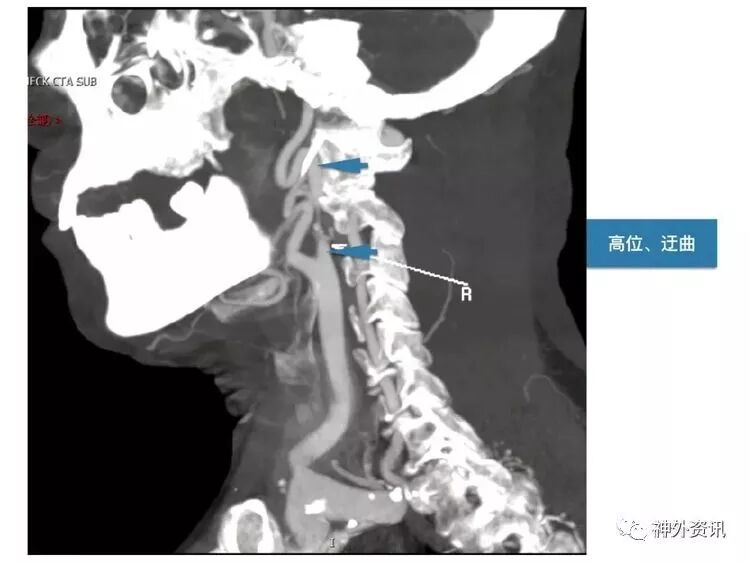

笔者的理解是:颈总动脉分叉部,位于下颌角水平以上(含下颌角水平)。此病例,颈内动脉狭窄部位,位于下颌角水平以上,接近颅底,属于高位CEA。

笔者认为,高位CEA手术的难点是:显露狭窄部位的远侧端(颅底侧方向)。